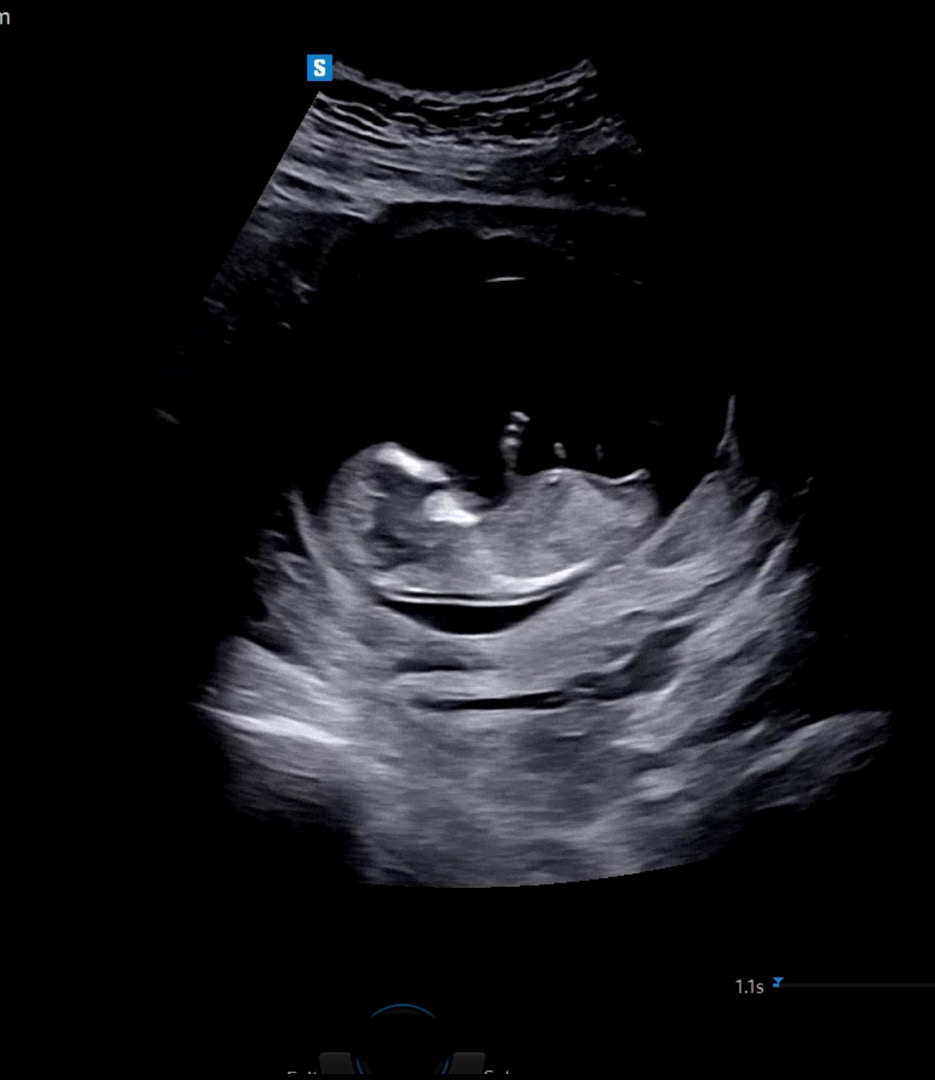

12주 2일 각도법 봐주세요! ❤️

사진에서 보시기엔 딸 각도인가요, 아들 각도인가요?